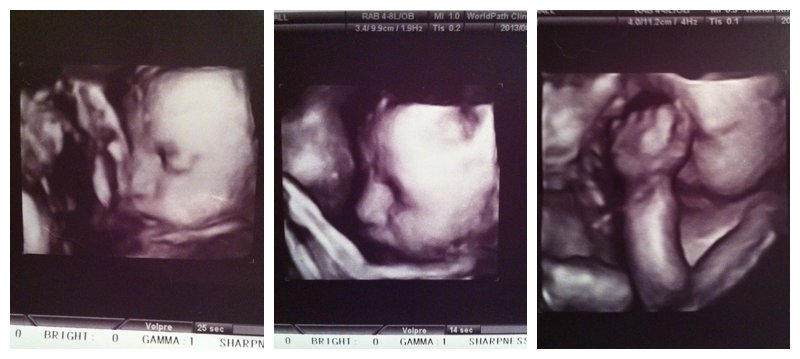

We’ve had a bit of doctor drama, unfortunately. Our wonderful doctor moved to a new, insanely expensive clinic that our insurance simply can’t cover, so we had to make a move. We met our new (highly recommended) OBGYN, Dr.Kong, as well as our bubbly midwife, Lin, at our 30 week appointment last week and couldn’t love them more! Such a relief for this first time mommy! During our appointment we had an ultrasound and FINALLY got a little peek at our sweet Isla’s face. I couldn’t stop the tears welling up in my eyes throughout the entire scan. Just look at those sweet chubby cheeks. And pouty little bottom lip. And delicate eyelids. AND that hair- I cannot believe my baby has long hair! Oh, I am so in love already!